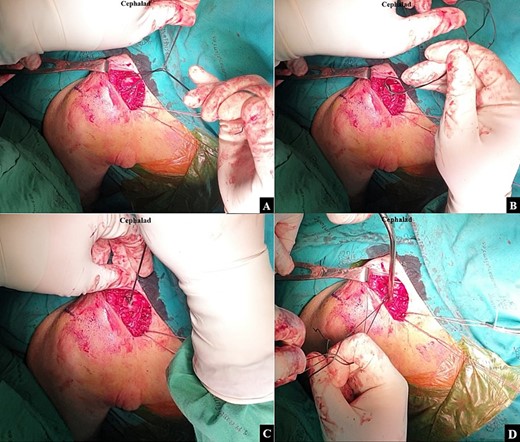

The surgical intervention was performed using a standard technique until exposing the coracoid base. An Ethibond No.2 suture was passed beneath the coracoid base from the medial side to the lateral side, and was then exchanged for a shuttle loop. An Ethibond No.5 suture was then folded, and the looped end passed beneath the coracoid base using the shuttle suture technique (Fig. 2). The operative field was adjusted to optimize visualization of the clavicle, and the clavicular fascia was incised along the clavicular bone to allow distinct demarcation of both the anterior and posterior clavicular borders. A right-angle clamp was utilized to create a tunnel from the coracoid base to the anterior clavicular border of the proximal fragment (Fig. 3A). The looped end of the Ethibond No.5 was then passed from the coracoid base to the anterior clavicular border of the proximal fragment using the right-angle clamp (Fig. 3B). The same technique was employed to create a second soft tissue tunnel from the coracoid base to the posterior clavicular border of the proximal fragment (Fig. 4A). The open end of the Ethibond No.5 was then passed from the coracoid base to the posterior clavicular border of the proximal fragment using the right-angle clamp (Fig. 4B). After a doubled-suture of the Ethibond No.5 was passed around the coracoid base and proximal fragment of the clavicle, a single square knot was thrown (Fig. 5A). The two open ends of the Ethibond No.5 were passed through the loop (Fig. 5B). The knot was dressed and slid down by pulling the two open ends of the Ethibond No.5 (Fig. 5C). The Nice knot was slowly tightened to incrementally slide the proximal fragment to the correct alignment with the distal fragment for the closed reduction (Fig. 5D) [1]. The fracture alignment was continually checked under fluoroscopy, and when a good alignment was achieved, the Nice knot was firmly tied.

After the doubled-suture of Ethibond No.5 was passed around the coracoid base and proximal fragment of the clavicle, (A) a single square knot was thrown. (B) The two open ends of the Ethibond No.5 were passed through the loop. (C) The knot was dressed and slid down by pulling the two open ends of the Ethibond No.5. (D) A Nice knot was slowly tightened to incrementally slide the proximal fragment to the correct alignment with the distal fragment for the closed reduction.

A second Nice knot was placed beside the first Nice knot to further secure and preserve the fracture alignment. The intra-operative fluoroscope images between before the closed reduction and after the closed reduction with the Nice knot technique are shown in Fig. 6A and B. Closure of the clavicular fascia and the anterior deltoid musculature was done with a Vicryl No.1 suture and the skin was closed using Nylon No.3.